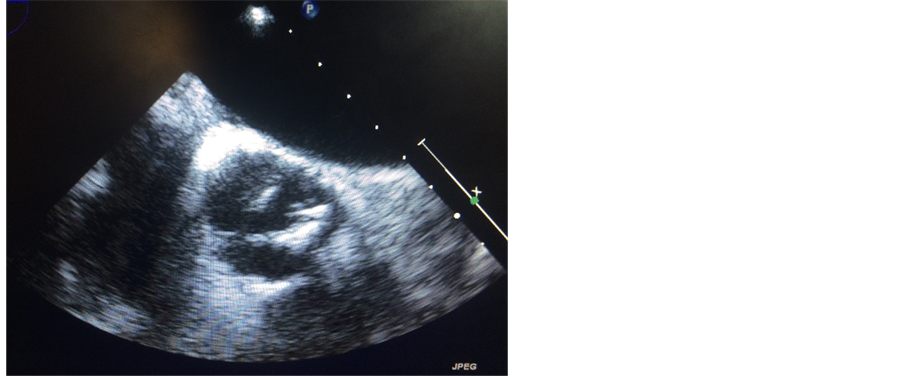

A 57-year-old man (body surface area, 1.9 m2) presented with exertional dyspnea. Transthoracic echocardiography revealed a calcified bicuspid aortic valve (Figure 1) with a mean pressure gradient of 63 mmHg and a calculated aortic valve area of 0.78 cm2, consistent with severe stenosis. Left ventricular ejection fraction was preserved at 65%. Preoperative coronary angiography demonstrated a single coronary artery above the right coronary cusp. The left coronary artery originated from the proximal portion of the right coronary artery (Figure 2). Three-dimensional computed tomography angiography demonstrated that the left coronary artery traveled anteriorly from its anomalous origin and across the conus arteriosus before anatomically correct bifurcation into left anterior descending and left circumflex vessels (Figure 3). No associated coronary artery disease was observed. Aortic valve replacement was performed via full median sternotomy. The ascending aorta was cannulated, and venous cannulation was performed through the right atrium. The patient’s core body temperature was slowly decreased to 35.5˚C. Myocardial protection was achieved using a combination of antegrade and retrograde cold bloodcardioplegia. The annulus sized to a 23 valve. The right coronary artery ostium was identified above the right coronary cusp via preoperative three-dimensional computed tomography angiography. The right coronary artery ostium was only 7 mmabove the annulus. We modified the procedure because of this proximity and the associated risk of coronary ostium occlusion if we set the valve supra-annularly. The 21-mm Aortic Magna Ease Valve (Edwards, Inc., Irvine, CA) was placed intra-annularly using everting sutures. The patient recovered uneventfully and was discharged home on postoperative day 7. He provided written informed consent for publication of this case report and all accompanying images.

Figure 1. Severely calcified bicuspid aortic valve.